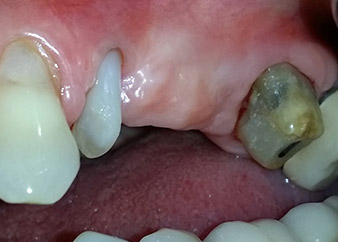

A 58-year-old female patient complained of pain and increased mobility of her bridge abutment tooth 24. Periodontal inflammation was present with pocket depths of 7 mm mesiobuccally and more than 12 mm distally, as well as third-degree furcation involvement. Moreover, the radiograph revealed an extensive periodontal lesion around the apical region of the (alio loco) endodontically pretreated tooth 24 (Fig. 1).

One year earlier, teeth 25 and 26 had been extracted due to trauma and for endo-perio reasons, prior to the placement of the bridge. A combined endo-perio lesion was diagnosed for tooth 24, of unclear aetiology. The patient wanted to keep her bridge abutment teeth 24 and 27 and would not accept a final, or even temporary, removable prosthesis. Therefore, it was agreed to make all efforts to retain both teeth, in spite of their poor prognosis as based on radiological and clinical findings.

Placement of two submerged implants was planned at sites 25 and 26, in a surgical session with open periodontal debridement and apicoectomy of tooth 24. Due to the vertical bone deficiency at the future implant site, an internal sinus augmentation was also planned.

Following topical medication with 25 % metronidazole gel (Elyzol) in the pockets of tooth 24, causal treatment with full-mouth periodontal disinfection therapy was initiated. The orthograde root-canal treatment was revised by means of thermoplastic gutta-percha obturation, a fiberglass post and a composite core. The bridge was recemented out of occlusion to allow undisturbed healing of the GTR and GBR sites.